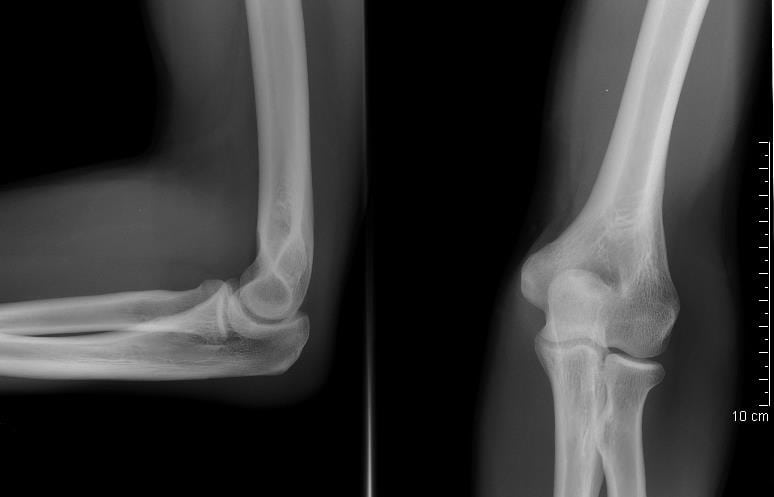

При выставлении диагноза врач учитывает результаты рентгенографии, МРТ, КТ, биохимических исследований крови, синовиальной жидкости. Лечение тендинита локтевого сустава проводится консервативными методами. Пациентам рекомендован прием НПВС, анальгетиков, физиотерапевтические процедуры, массаж, ЛФК. При неэффективности консервативной терапии показано хирургическое вмешательство с иссечением поврежденных тканей сухожилия.

Выставить диагноз на основании только внешнего осмотра помогает предшествующая травма. Врач предполагает развитие тендинита, если пациент профессионально занимается спортом или по роду службы выполняет монотонные движения руками. Для подтверждения диагноза, оценки степени воспалительного процесса назначается ряд инструментальных исследований:

- рентгенография. Полученные изображения позволяют оценить состояние костных, хрящевых тканей. При обнаружении деформации локтевого сустава врач предполагает, что причиной тендинита стал артрит или остеоартроз;